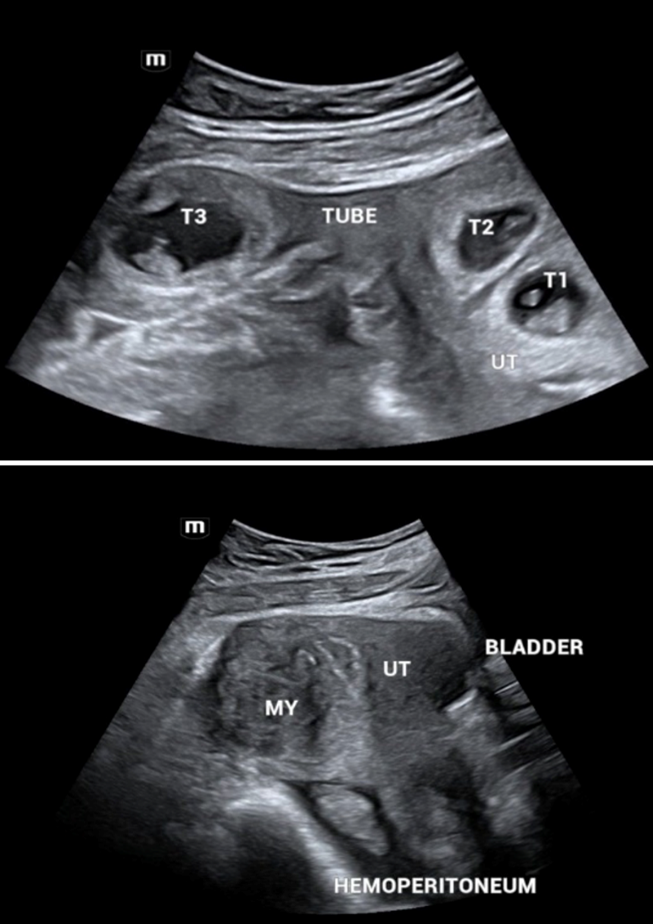

A 39-year-old female patient, married for two years, gravida two, nulliparous, consulted the Assossa Medical Polyclinic in December 2023 for fertility care. Her history included a miscarriage shortly after her wedding. The physical examination was unremarkable, and ultrasound showed fibroids: one antero fundal, type 3-5, measuring 41×30 mm, and two antero corporeal, type 4 and 3, measuring 25×19 mm and 18×12 mm respectively. Hysterosalpingography showed bilateral tubal permeability. She was also treated at the same clinic for an upper genital infection. In June 2024, she underwent ovulation induction with Clomiphene Citrate 50 mg daily from day two to six of the menstrual cycle, followed by progesterone twice a day 200 mg from day 17 to day 27 of the menstrual cycle. More than a month later, she went back to the hospital for a delay in her periods, and the pregnancy test was positive. A first ultrasound scan showed two intrauterine gestational sacs with no embryonic echoes. A second ultrasound two weeks later showed a heterotopic pregnancy with two intrauterine sacs and a sac in the right tube (Figure 1). The patient was transferred to the University Hospital of Kinshasa.

On admission, she was lucid, blood pressure was 125/80 mmHg, slightly tachycardic at 104 beats per minute, palpebral conjunctivae moderately coloured, abdomen not bloated, soft and depressible with tenderness to the right iliac fossa. On speculum examination, the cervix appeared healthy, the Douglas was not bulging, and on vaginal examination, the uterus was enlarged, with palpation of a 2 cm right adnexal mass, tender and soft. Ultrasound showed an evolving intrauterine twin pregnancy (with cardiac activity) of eight weeks, an evolving right ampullary pregnancy (with cardiac activity) with marginal trophoblastic detachment, moderate intra-abdominal bleeding ion and a large 53×49 mm type 5 postero fundal fibroid.

Figure 1: Ultrasound findings: A shows three gestational sacs, two of which are intrauterine (UT) twins (T1, T2) and one in the right tube (T3). B shows a sagittal section of the pelvis. A posterofundal fibroid (MY) and an effusion in the Douglas suggesting hemoperitoneum were noted